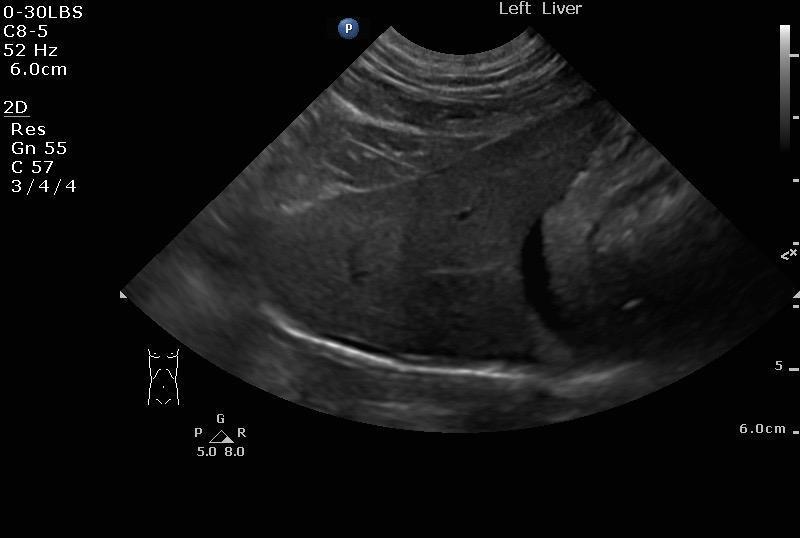

Pancreatic lymphoma confirmed with cytology in a 10 year old MN DSH cat

A 10-year-old MN DSH was presented for evaluation of decreased appetite and lethargy. Abdominal effusion was present on physical examination. Serum biochemistry showed azotemia.

Image Interpretation

The right pancreatic base revealed a 2.25 x 3.0 cm mass with irregular, nodular, ill defined surrounding changes throughout the omentum. Ultrasound-guided FNA was performed without complication. The mass appeared to be adhered to the duodenum.

A large amount of mildly echogenic free fluid was noted.